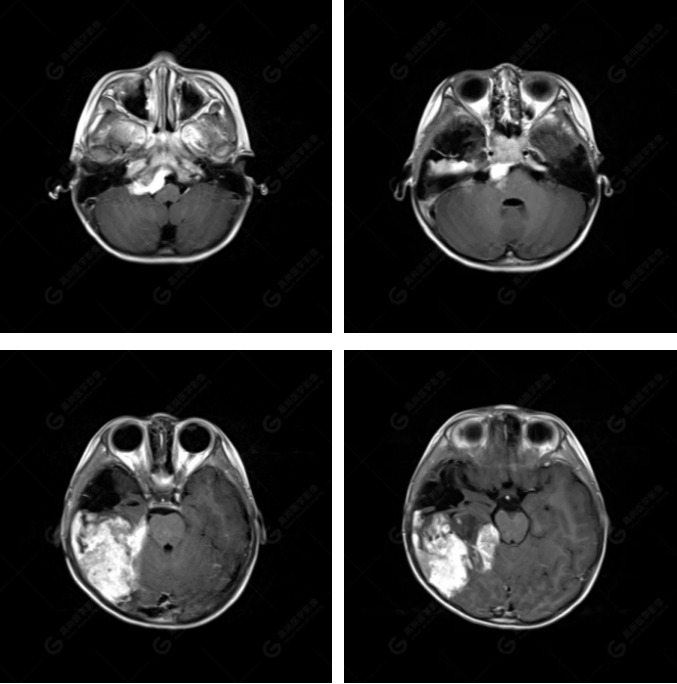

右側(cè)顳葉腫瘤切除術(shù)后(具體不詳):右側(cè)顳部骨質(zhì)不連續(xù)呈術(shù)后改變,右側(cè)顳葉術(shù)區(qū)見(jiàn)片狀長(zhǎng)T1長(zhǎng)T2信號(hào)影,F(xiàn)LAIR呈低信號(hào);術(shù)區(qū)后方右側(cè)顳枕葉見(jiàn)一巨大占位性病變影,邊界欠清,大小約6.2×5.8×4.3cm(前后×左右×上下),信號(hào)不均勻,T1WI呈等稍低信號(hào)間雜少許高信號(hào),T2WI呈高稍低混雜信號(hào),DWI示部分病灶彌散受限,相應(yīng)ADC圖減低,磁敏感序列見(jiàn)部分呈極低信號(hào),增強(qiáng)掃描可見(jiàn)明顯不均勻強(qiáng)化,鄰近硬腦膜及小腦幕增厚并明顯強(qiáng)化;另延髓右前方及右側(cè)橋小腦角區(qū)見(jiàn)一不規(guī)則形異常信號(hào)影,大小約3.2×1.3×3.7cm(左右×前后×上下),呈長(zhǎng)T1稍長(zhǎng)T2信號(hào),F(xiàn)LAIR呈等信號(hào),DWI未見(jiàn)受限,增強(qiáng)后明顯均勻強(qiáng)化,鄰近腦膜明顯強(qiáng)化。鄰近腦實(shí)質(zhì)及右側(cè)顳角明顯受壓;左側(cè)大腦半球未見(jiàn)局灶性信號(hào)異常,中線結(jié)構(gòu)稍左移。

右側(cè)顳葉腫瘤切除術(shù)后:現(xiàn)術(shù)區(qū)后方右側(cè)顳枕葉及延髓右前方占位,右側(cè)顳枕部硬腦膜及小腦幕明顯強(qiáng)化,結(jié)合既往影像資料,考慮為胚胎源性惡性腫瘤,如非典型畸胎樣/橫紋肌樣瘤(AT/RT)或原始神經(jīng)外胚層腫瘤(PNET)。

非典型畸胎樣/橫紋肌樣瘤(AT/RT) 是一種高度惡性中樞神經(jīng)系統(tǒng)腫瘤,臨床罕見(jiàn),臨床表現(xiàn)無(wú)特異性,好發(fā)于 5 歲以下兒童,尤以 3 歲以下多見(jiàn),在兒童原發(fā)性中樞神經(jīng)系統(tǒng)(CNS)腫瘤中占 1%~3%。該腫瘤體積一般較大,幕上大于幕下,有明顯的占位效應(yīng)。該腫瘤成分復(fù)雜,囊變、出血、壞死常見(jiàn)。因此 AT/RT信號(hào)混雜,囊性部分呈 T1WI低、T2WI高信號(hào),增強(qiáng)后不強(qiáng)化;若瘤體出血,囊內(nèi)可見(jiàn)T1WI稍高信號(hào)、T2WI低信號(hào),實(shí)性部分在 T1WI上呈混雜等、低信號(hào),在T2WI 及 T2-FLAIR上呈混雜等高信號(hào),增強(qiáng)掃描后大部分呈環(huán)形條帶樣明顯強(qiáng)化,中心壞死區(qū)不強(qiáng)化。另外,該腫瘤實(shí)性成分在DWI上呈高信號(hào),說(shuō)明腫瘤細(xì)胞核密集,水分子擴(kuò)散明顯受限,提示該腫瘤惡性程度高,容易復(fù)發(fā)及轉(zhuǎn)移。